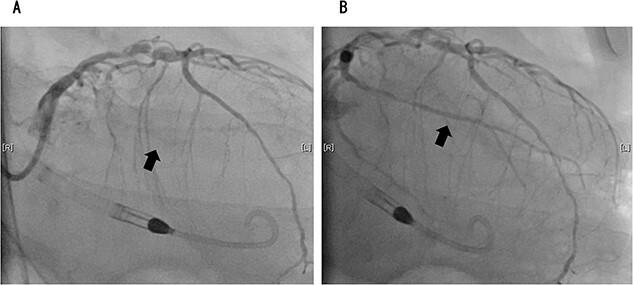

Postoperative hemodynamic support with an Impella 5.0 was effective in a man who underwent lung lobectomy for lung cancer and cardiogenic shock. A 75-year-old man presented to hospital with an abnormal chest shadow on radiography. After thorough examination, the patient was diagnosed with lung cancer, and left lower lobectomy was performed. On the 2nd postoperative day, the patient experienced cardiac arrest because of a sudden drop in saturation of percutaneous oxygen. After a third defibrillation, his heartbeat resumed, and he was intubated and placed on a ventilator. Coronary angiography revealed acute coronary syndrome and the patient fell into a state of shock, which required venoarterial extracorporeal membrane oxygenation (VA-ECMO) support. Nevertheless, the circulatory dynamics are unstable, and Impella 5.0 was introduced. VA-ECMO and the Impella 5.0 were discontinued on the 6th and 8th postoperative days, respectively. The patient was eventually transferred to a nearby facility for further rehabilitation 109 days later.

一名因肺癌接受肺叶切除术并发生心源性休克的男性患者,使用Impella 5.0进行术后血流动力学支持取得了良好效果。一名75岁男性因胸部X光片显示异常阴影入院。经过全面检查,患者被诊断为肺癌,并接受了左下肺叶切除术。术后第2天,患者因经皮血氧饱和度突然下降发生心脏骤停。第三次除颤后,患者心跳恢复,随后进行气管插管并使用呼吸机。冠状动脉造影显示急性冠状动脉综合征,患者陷入休克状态,需要静脉-动脉体外膜肺氧合(VA-ECMO)支持。然而,循环动力学仍不稳定,于是引入了Impella 5.0。VA-ECMO和Impella 5.0分别在术后第6天和第8天停用。最终,患者在109天后被转至附近机构进行进一步康复治疗。